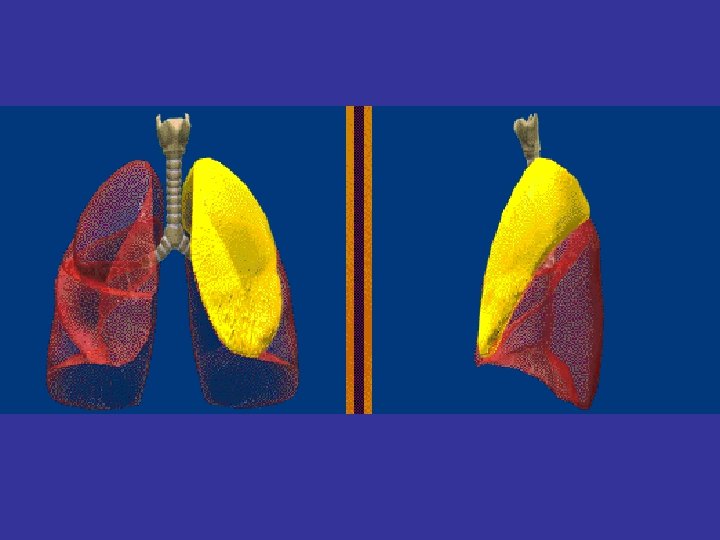

Lobes and Fissures